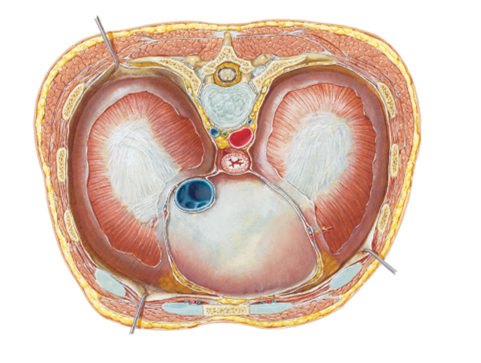

show what the superior thoracic aperture and inferior thoracic aperture are?

notice how in the first picture the esophagus and trachea, nerves and BV's are popping through

what does the superior thoracic aperture contain?

what does the inferior thoracic aperture allow?

- Superior...contains esophagus, trachea, nerves & blood vessels that supply the head, neck and UE

- Inferior...allows the esophagus, IVC (inferior vena cava) and aorta to pass inferior to abdominal cavity